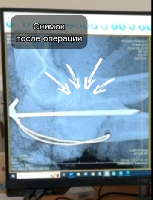

Мобильный рентгенаппарат + оцифровщик. Получение рентгеновского изображения на экране ноутбука. Вариант за 1,4 миллиона рублей под ключ.

Мобильный рентгенаппарат с печатью рентгенограмм на рентгеновской пленке. Цена 700000 рублей.